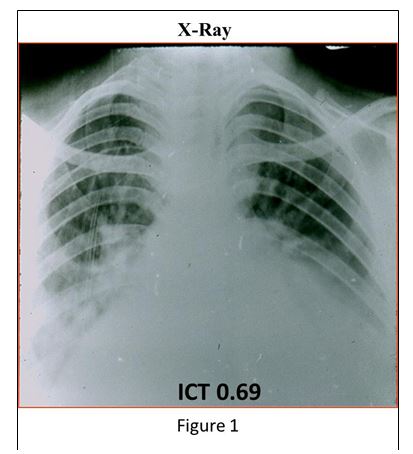

The chest X-Ray shows important enlargement of the heart with pulmonary edema (Figure 1).